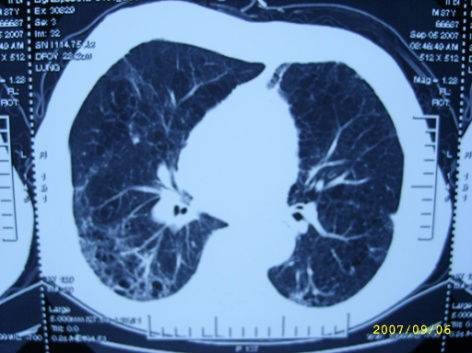

20天后,患者胸水消失,肺部炎症减轻、心影缩小,症状明显好转出院。

治疗后